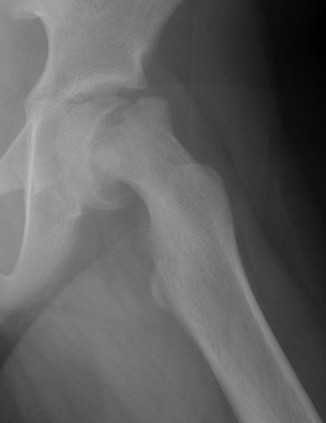

Xray

Normal with transient synovitis

Hip subluxation with septic arthritis

Septic arthritis

SCFE / Perthes